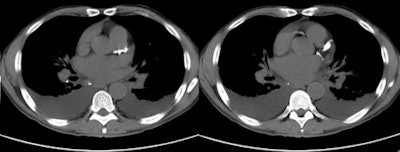

![]() |

| Noncontrast images of the thorax in a patient presenting with dyspnea demonstrate bilateral pleural effusions and four-vessel coronary calcification (i.e., the left main, left anterior descending, circumflex, and right coronary arteries). Images courtesy of Kim Williams, MD. |

Three experienced readers working independently reviewed all of the images for cardiovascular findings. According to the results, coronary calcium was present in 202 patients (59% of the group), but coronary artery calcium was recorded as being present in the final radiology report in just 44% of patients with calcium.

As for the most dangerous arterial segments in which to have stenoses, aka "the widowmakers," calcium was visible in the left main coronary artery in 139 patients but was reported in only 0.7% of the cases, Williams said. Calcium was visible on review of the left anterior descending artery images in 188 patients, but it was reported by name in only 1.6%.